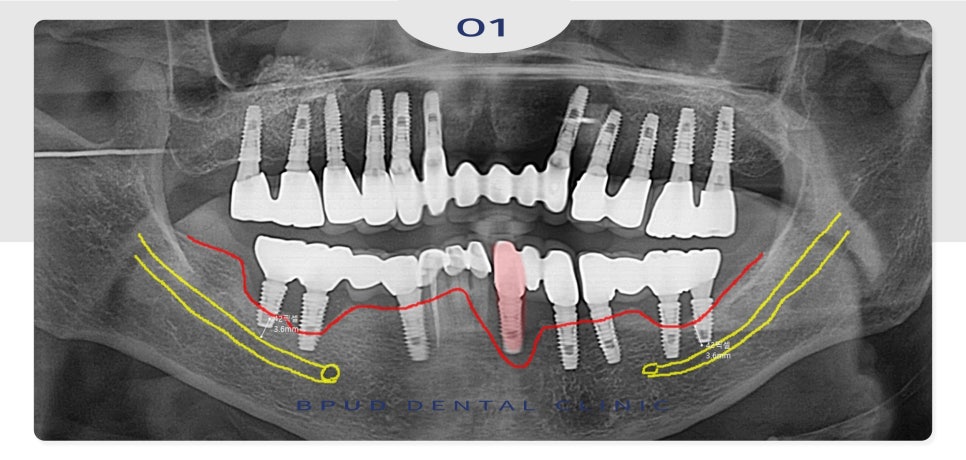

이미 양쪽 아래 어금니 부위와 앞니에

심한 골 소실이 진행되어 신경관까지의 거리가

3mm 정도 남아 제거가 필요한 상태였는데요.

따라서 전체적인 치주치료와

기존 임플란트 제거 후 재식립을 설명드렸습니다.